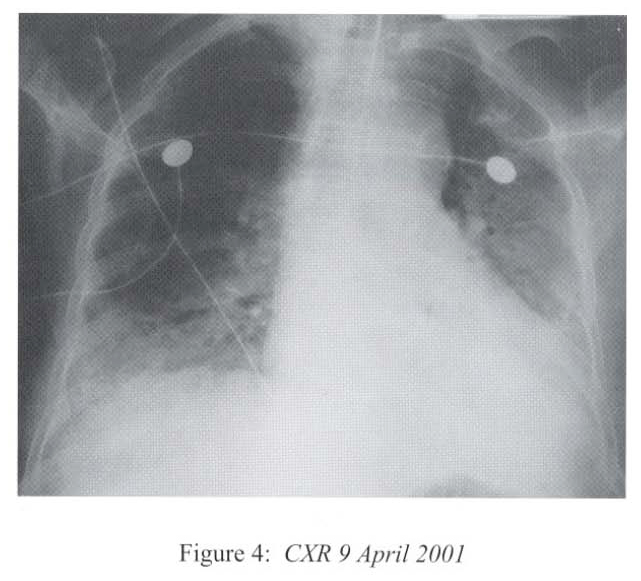

The respirology team was consulted at this time and we took over the case and managed her in the High Dependency Unit. The differential diagnoses included uncontrolled bacterial or fungal pneumonia, Pneumocystis carinii pneumonitis, viral pneumonitis, autoimmune pneumonitis, massive pulmonary embolism and massive pulmonary haemorrhage. She was treated with broad-spectrum antibiotics (piperacillin/tazobactam, amikacin) together with intravenous gancyclovir and cotrimoxazole. Supportive treatment included inotropes infusion, peritoneal dialysis, parenteral nutrition, and optimization of mechanical ventilation. Hydrocortisone was continued since she has been on systemic steroid for 3 months and the haemodynamic state was unstable. Bronchoscopy via the endotracheal tube showed copious mucoid secretions arising from both lung bases, and there was patchy mucosal excoriations involving the lower lobes. There was no sign of pulmonary haemorrhage. No transbronchial biopsy was attempted as she was on positive pressure ventilation and in critical state. CXR after bronchoscopy showed rapid resolution of pneumonia shadows in multiple areas (Figure 4).

Radiological features are also diverse and variable 15,16.On the chest radiograph, early signs include miliary shadows, diffuse reticular interstitial opacities, patchy alveolar opacities, segmental or lobar opacities. In the advanced stage, there can be extensive airspace shadows affecting both lungs, with occasional pleural or pericardial effusion. Without treatment, ARDS quickly evolves. Rarely, ARDS develops after antihelminthic treatment due to release of toxic breakdown products 17.On the abdominal radiograph, there can be thickened mucosal folds, segmental small bowel dilatation or perforation. Among all these variable radiological features, a characteristic pattern of Strongyloides hyperinfection has been described by the radiologists of Hong Kong, which consist of fleeting and rapidly changing CXR signs, predominant small bowel abnormality on AXR, and close temporal relationship of CXR & AXR signsl8. Detection of larvae in stool or other specimens is difficult (Table 1). Serological diagnosis19 is an attractive alternative but it is not available in Hong Kong.